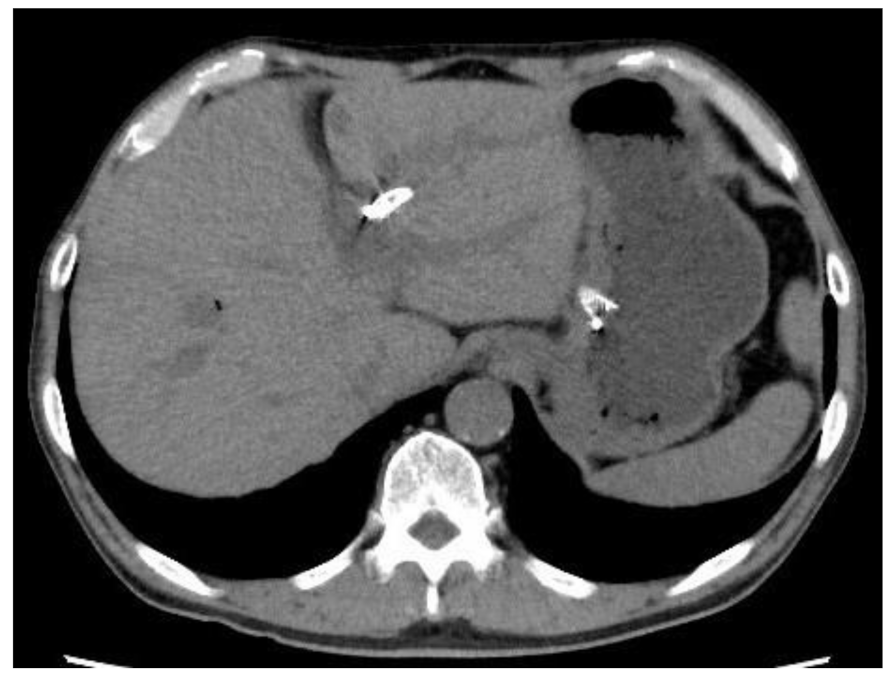

4. Discussion